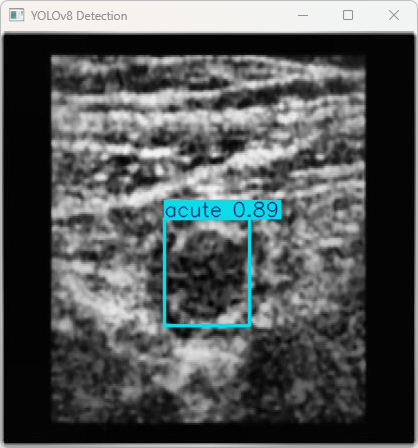

(2)cv2.imshow(“YOLOv8 Detection”, res):使用OpenCV显示检测后的图片,窗口标题为“YOLOv8 Detection”。

执行imgTest.py代码后,会将执行的结果直接标注在图片上,结果如下:

这段输出是基于YOLOv8模型对图片“imagetest.jpg”进行检测的结果,具体内容如下:

检测结果:检测到1个目标:acute (急性阑尾炎的病变)

总结:

该模型成功检测到了急性阑尾炎,并且整个处理过程非常高效,图像的预处理、推理和后处理时间均较短,适用于临床环境的实时应用。